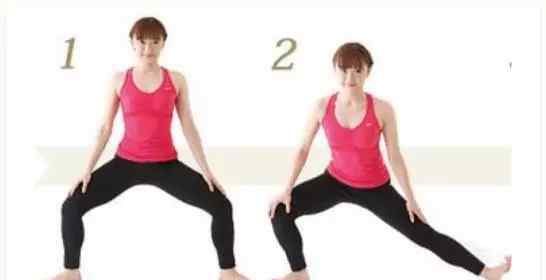

腿部伸展

你需要用手弯曲你的臀部和膝盖。如果觉得累,可以采用坐姿或卧姿,双腿伸直,用毛巾勾住脚趾和前脚掌,将毛巾拖到身体上,使双脚向后弯曲。

小腿后肌群牵引

站立膝关节伸直弯曲,重点是腿后肌肉群的牵拉活动。